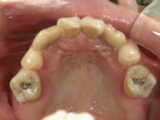

● 臼歯部の後方移動

臼歯を後方に牽引し、移動させることでスペースを確保し歯列を整えます。

臼歯にリンガルアーチという装置を装着し、ミニインプラントを固定源に臼歯を後方に牽引します。

前突が改善し、きれいな歯並びになりました。

臼歯が後方に下がり、臼歯と小臼歯の間にスペースができました。唇側にワイヤ-をSETし、前歯の歯並びの改善を併行して行います。